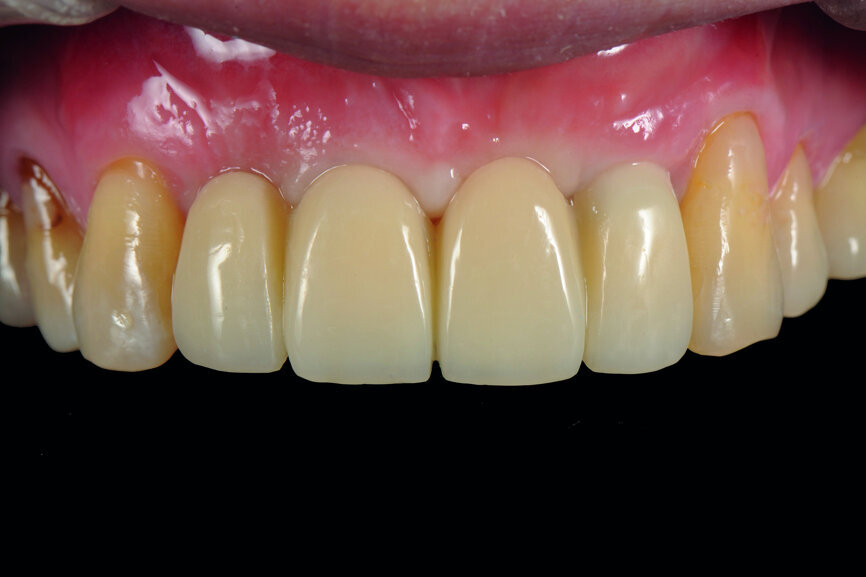

Fig. 43: Frontal view of the anterior teeth just after delivery.

The cast model was scanned step by step to obtain a digital model and this was integrated with a virtual articulator. The anterior guidance of the virtual articulator was set according to the data from the provisional restoration. Next, the design was completed on computer and the titanium-based zirconia abutment and fixed zirconia bridge produced via CAM. After staining and glazing, the final restoration was completed (Figs. 34–41). The final restoration demonstrated a good outcome, both aesthetically and functionally (Figs. 42–50).